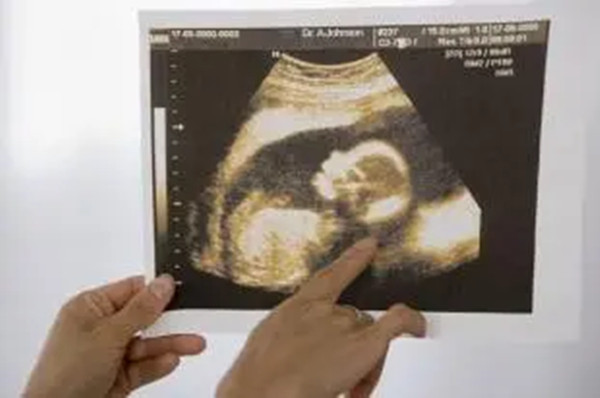

怀孕判断男孩女孩B超数据图准不准?如何通过B超图像来判断宝宝的性别?

怀孕是每个女性生命中的重要阶段,而宝宝的性别也是一个备受关注的话题。在过去,人们只能通过怀孕期间的种种传统迹象来猜测宝宝的性别,比如胎动、食欲增加等等。然而,随..

怎么看孕妇B超单图像判断男女?B超图像判断男女哪些因素影响?

在过去,人们只能通过孕妇的体征和传统的方法来预测胎儿的性别。然而,随着科技的进步,现代医学提供了一种更准确的方法来判断胎儿性别——B超技术。本文将介绍怎么看孕妇B..